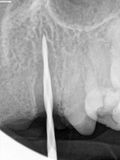

fredlibc | all galleries >> Galleries >> NSankhyan - immediate 12,11, and 22 > R3.jpg

R3.jpg